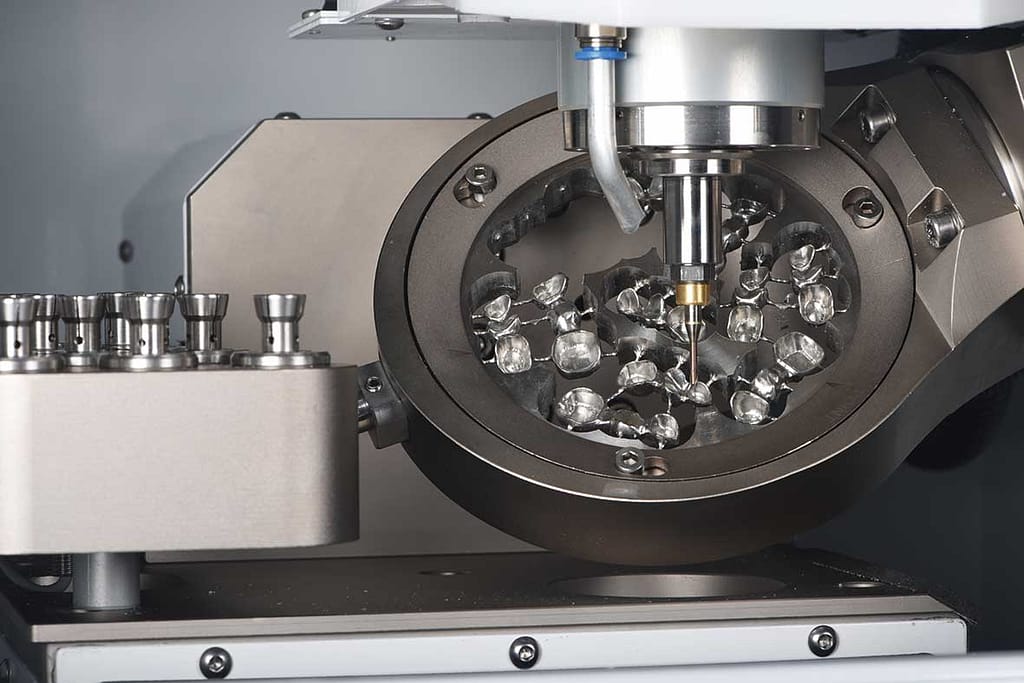

Tecnología de punta

- Radiografías digitales y tomografía 3D: planificación precisa del implante.

Los implantes dentales realizados en Perú cumplen estándares internacionales, respaldados por tecnología avanzada, especialistas capacitados y un enfoque humano.